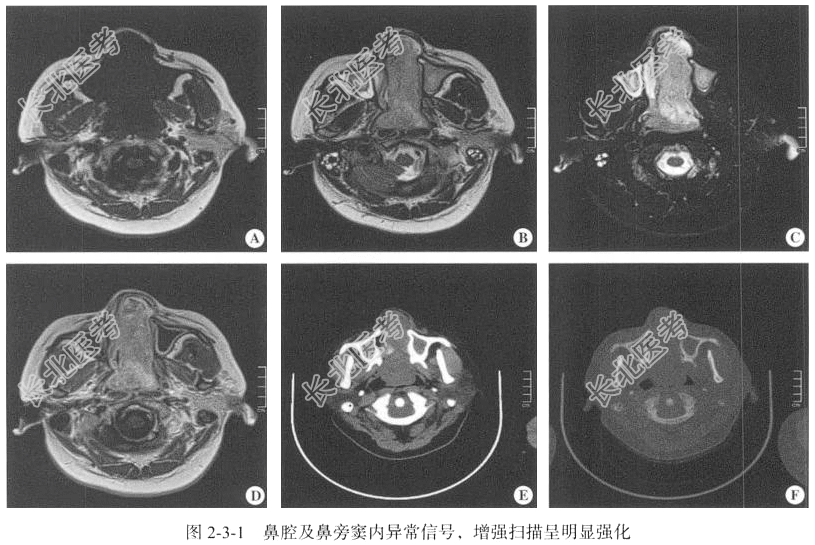

- [材料题] 【临床病史】女性,34岁。鼻塞及流涕9年,加重3个月。

【专科查体】右侧鼻前庭可见脓性分泌物,鼻中隔右侧偏曲阻塞鼻前孔,左侧鼻前庭可见巨大蓝紫色肿物阻塞鼻前孔,双侧鼻甲及鼻道无法窥及。

【鼻腔MRI检查】仰卧位,横断位扫描,包括T₁WI、T₂WI及T₂WI脂肪抑制序列,扫描范围自上齿槽至额窦以下,扫描层厚为5mm,层间隔0.5mm,矩阵256×512;以冠状位T₂WI,矢状位T₂WI FLAIR序列平扫后行横断位、冠状位及矢状位的增强扫描。

【影像图片】见图2-3-1。

【手术所见】左侧鼻腔内肿物,色泽灰白,质韧,鼻中隔被肿瘤压迫,骨质吸收缺如,呈穿孔状态,右侧中鼻甲内侧面受压。部分筛窦呈息肉样改变。

【病理所见】肉眼:(左侧鼻腔肿物)不整组织一堆,大小为4cm×3cm×2cm,呈灰白灰黄色、质中。病理诊断:(左侧鼻腔肿物)结合HE染色及免疫结果,符合嗅神经母细胞瘤,大小为4cm×3cm×2cm。镜下可见小圆形细胞、梭形细胞、细胞核、神经束等结构,肿瘤细胞核深染,胞质少,细胞密集排列,局部可见肿瘤性坏死,异型性明显(图2-3-2)。免疫组化结果A3:CD3(-),CD20(-),S-100(-),A103(-),HmB45(-),Vim(+),AE1/AE3(-),CAM5.2(-),Ki-67(40%+),CD34(-)Desmin(-),SOX10(少+),Myogenin(-),MyoD1(-),SMA(-),Syn(+),CgA(+),CD56(-),P63(-),CD99(-),CD38(-),WT1(-)。

【病理诊断】嗅神经母细胞瘤。